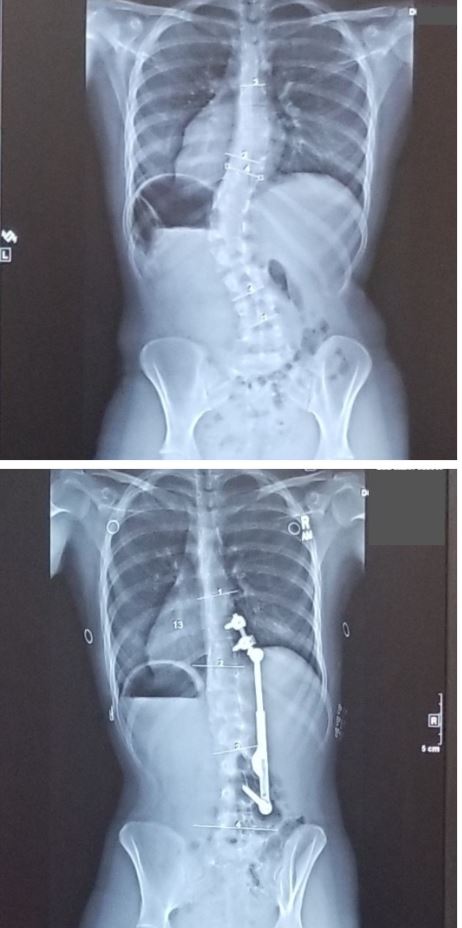

ApiFix is an FDA-approved surgical treatment for moderate scoliosis in adolescents. It works by gently straightening the spine using a flexible rod and a self-adjusting design. Unlike traditional spinal fusion, ApiFix allows for some movement and flexibility even after surgery.

This approach uses just a few small incisions and avoids the need to fuse large sections of the spine, making it a less invasive option that preserves spinal motion.

- Have a spinal curve between 35 and 60 degrees: This range is ideal for ApiFix’s corrective capabilities. Curves below 35 degrees may not need surgery, while curves above 60 degrees may require a more traditional approach.

- Have flexible curves that can be corrected without spinal fusion: ApiFix relies on the spine’s natural flexibility to gradually guide it into alignment. Flexibility is typically assessed through bending X-rays or other imaging studies.

- Single curves classified as Lenke 1 (thoracic major curve) or Lenke 5 (thoracolumbar/lumbar major curve)

- Cobb angle 35 – 60 degrees

- Curves reduce to ≤ 30 degrees on lateral side-bending x-rays